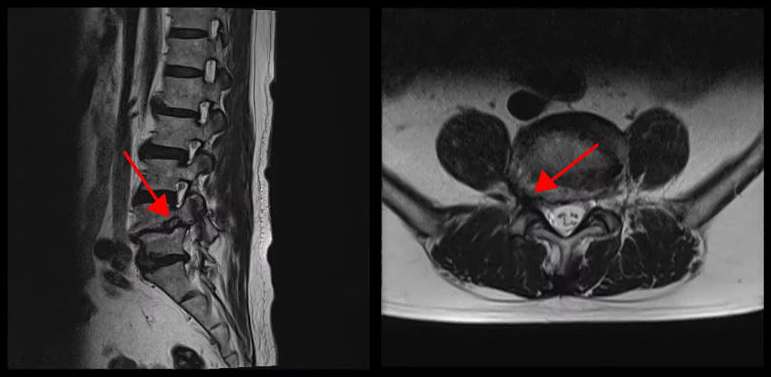

<4-5번 척추전방전위증>

이 환자분의 허리 MRI를 보면 4번, 5번 오른쪽에 심한 추간공협착증과 2단계의 척추전방전위증이 있는데, 특히 척추전방전위증 때문에 추간공이 많이 좁아져 있는 상태입니다. 또 왼쪽의 다른 마디에 디스크 파열이 있으나 환자분이 왼쪽으로는 증상이 전혀 없는 것으로 보아 이 디스크 파열은 통증을 일으키지 않는 무증상의 디스크 파열입니다.

이렇듯 4번, 5번 마디의 심한 추간공협착증과 척추전방전위증으로 인해 이 환자분은 다리에 마비가 왔고, 발목에 힘이 빠져 거의 걷지 못하는 상태였습니다. 새벽에 잠에서 깨 화장실을 갈 때는 네 발로 기어갈 정도로 증상이 심했습니다. 신경주사도 많이 맞아봤지만 통증이 전혀 줄지 않아서 결국 수술을 결심하셨는데요. 대학병원을 비롯해 정형외과 및 신경외과 등 아홉 군데 병원에서 진료를 받았지만, 어려운 수술이라고 말하면서 척추유합술, 감압술 등 병원마다 제시하는 수술방법이 다 달라 큰 혼란을 겪으셨습니다. 게다가 수술 후 후유증이나 잔존 증상에 대한 물음에 ‘있을 수도 있고 없을 수도 있다’라는 의사의 말에 수술을 고민하던 중 마지막이라는 생각으로 저희 모커리에 내원하셨습니다.